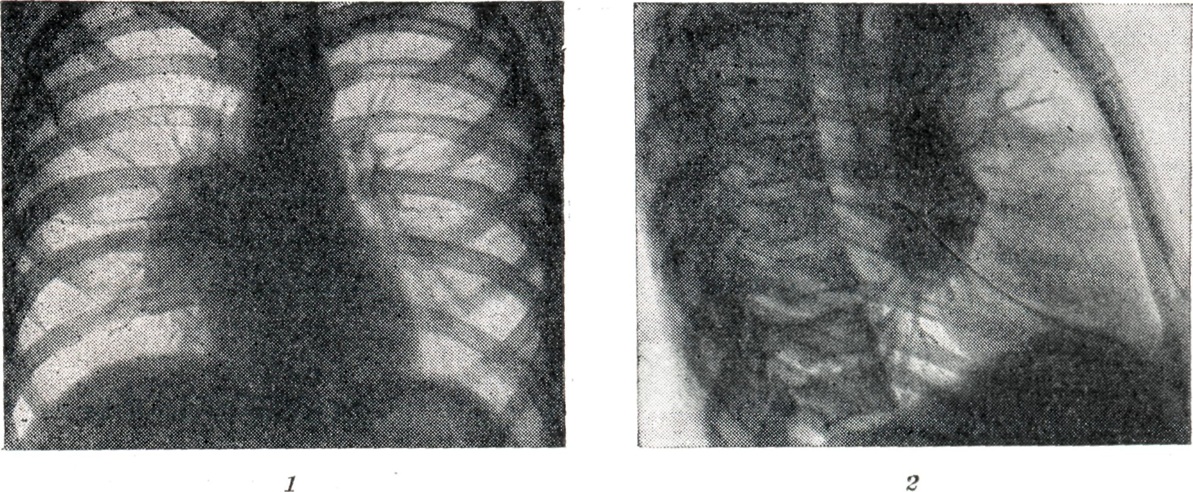

Рис. 3.

Рентгенограмма грудной клетки того же больного, что и на рис. 2, в боковой проекции. Кроме опухолевидного увеличения лимфатических узлов справа, видна утолщённая междолевая плевра.

Проекции бронхов менее отчётливы, тень корня почти сливается с тенью средостения. Наружная волнообразная или бугристая граница деформированного корня проецируется в виде отчётливой, хотя и не всегда резкой линии, что зависит от отсутствия или наличия воспалительных изменений в капсуле лимф, узлов. При одностороннем опухолевидном Б. изменения корня противоположного лёгкого менее выражены (рис. 2), на стороне поражения лёгочный рисунок несколько усилен, прилежащие листки междолевой плевры уплотнены (рис. 3).

Рис. 5.

Рубцовое уплотнение корней лёгкого после перенесённого двустороннего бронхаденита. Видна плотная тяжестость корней (рентгенограмма).